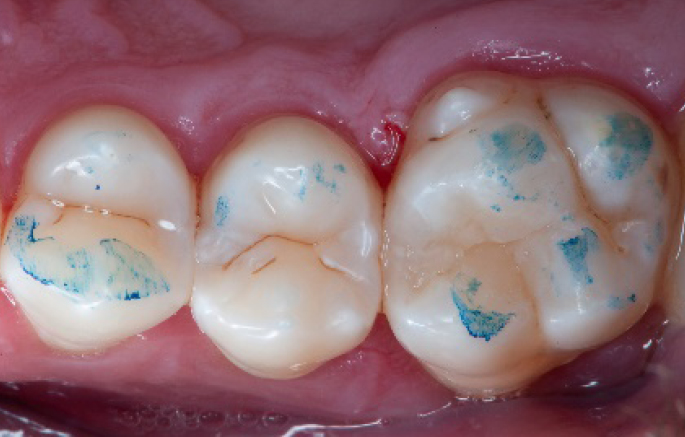

Step 11:

Occlusal surface restored using Spectra ST4 composite in shade A2.

Step 12:

The situation after rubber dam removal.

Step 13:

Occlusal check